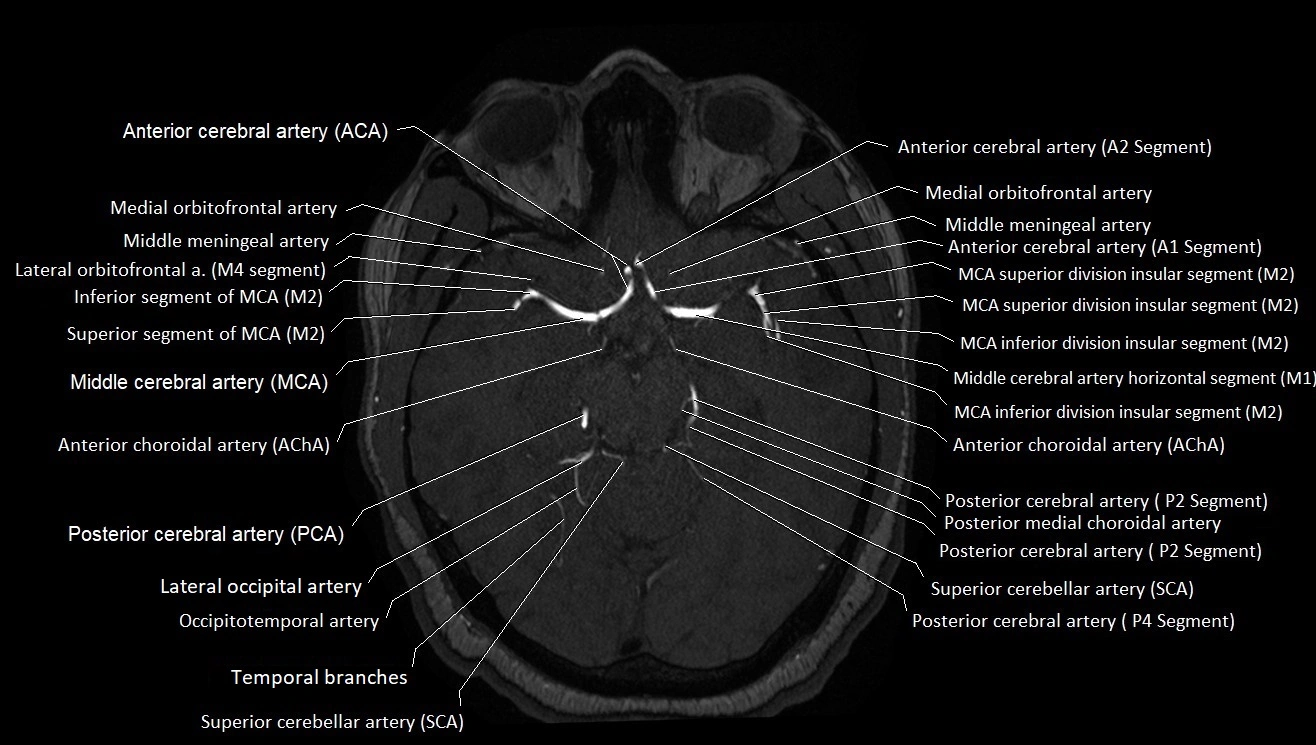

MRA (Magnetic Resonance Angiography):

• Flow-related enhancement makes the AChA appear as a bright, linear vascular signal against suppressed background

• High sensitivity for origin and proximal course; distal branches may be too small to resolve

• Detects stenosis, occlusion, aneurysm, AVM feeders

MRI images

image